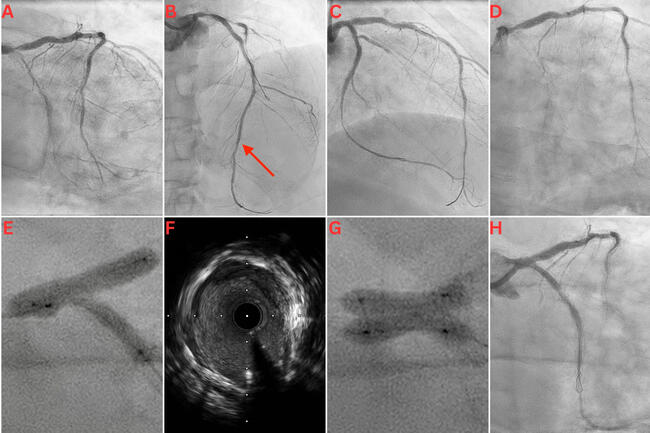

A 65-year-old man with a history of extensive percutaneous coronary intervention (PCI) because of recurrent in-stent restenosis (ISR) presented with a non-ST segment elevation myocardial infarction (NSTEMI). Coronary angiography revealed severe ISR in his left main coronary (LMCA), left anterior descending (LAD), and left circumflex (LCx) arteries (Figure A and B). Intravascular ultrasound (IVUS) revealed an LMCA diameter of 5.5 mm, deep vessel calcification, and severe neo-intimal hyperplasia, with only mild stent underexpansion. IVUS-guided PCI of the LMCA, LAD, and LCx was performed using a scoring balloon, a 5.5-mm noncompliant (NC) balloon in the LMCA, and 4.0 and 3.5-mm Paclitaxel drug-eluting balloons (DEB) in the LAD and LCx, respectively. There was a good final angiographic result following this intervention (Figure C).

The patient represented 5 months later with an NSTEMI. Angiogram revealed critical ISR of the recently treated LMCA bifurcation (Figure D). PCI was performed using NC and cutting balloons, followed by several applications of excimer laser coronary atherectomy (ELCA) in the LMCA, LAD, and LCx. Three-stage kissing balloon inflations (KBI) at the LMCA bifurcation were performed with a 4.0-mm NC balloon in the LAD and a 3.5-mm NC balloon in the LCx. There was significant waisting without complete balloon expansion (Figure E). IVUS showed calcification, stent recoil, and residual neo-intimal hyperplasia (Figure F, Video 1). Following prolonged inflations with 4.0 x 20-mm and 3.5 x 20-mm Paclitaxel DEBs in the LAD and LCx, respectively, two 4.0 x 10-mm OPN NC ultra high-pressure balloons (SIS Medical AG) were used individually for postdilation in both the proximal LCx and LAD; they were each inflated to 40 atm. Finally, KBI was performed in the LMCA/LAD/LCx bifurcation with the 2 OPN balloons to 20 atm each. There was complete balloon expansion with noticeable angiographic improvement (Figure G).

Following ELCA and balloon angioplasty, there was minimal tissue within the stents in either vessel. However, there was significant tissue behind the stent in the LCx, giving the appearance of moderate disease in the mid-LCx on the final angiographic images. Given there was a good minimal luminal area on IVUS, and the patient had a poor response to stents in the past with recurrent ISR, this was accepted as a good final angiographic result at the end of the procedure (Figure H, Video 2). The patient was discharged on dual antiplatelet therapy and colchicine for its antiproliferative effects. He remained well and asymptomatic on review after 6 months.